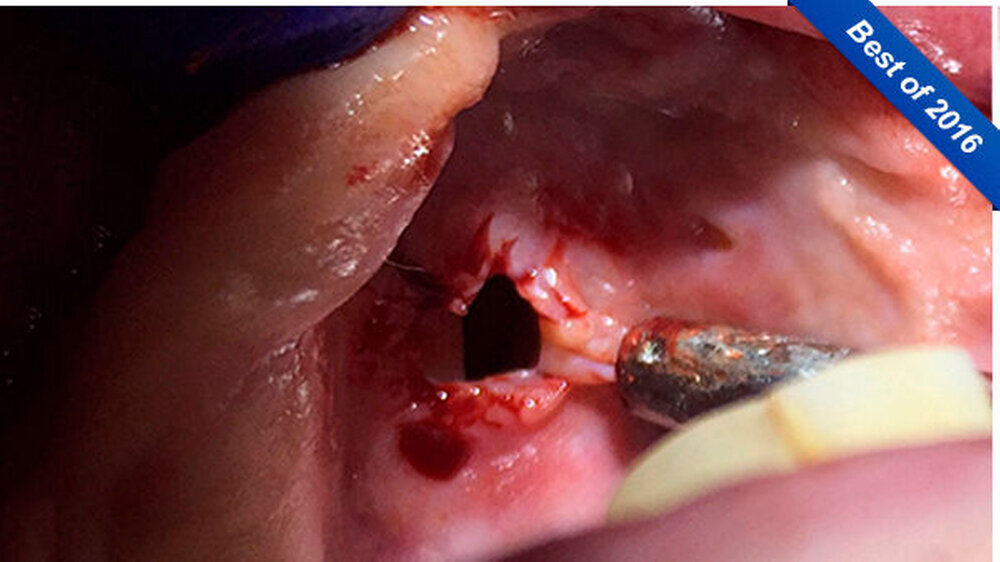

Der Gaumen war perforiert, was den anfänglichen Verdacht einer Mund-Antrum-Verbindung (MAV) bestätigte. Mit dem Verdacht auf eine Wegner`sche Granulomatose überwies die Zahnärztin die Patientin zum Internisten, der in der Blutuntersuchung jedoch nur leicht erhöhte ANA- und ANCA-Werte feststellen konnte, die den Verdacht auf eine Autoimmunerkrankung nicht bestätigten.

Die Patientin wurde dann über acht Wochen mit Clindamycin behandelt. Eine in der Zahnarztpraxis erfolgte plastische Deckung der MAV platzte nach zwei Tagen post operationem wieder auf. Ihr Allgemeinzustand verbesserte sich trotzdem erheblich. Im Unterschied zu vorher konnte sie den Weg vom Wartezimmer in den Behandlungsstuhl selbstständig gehen.